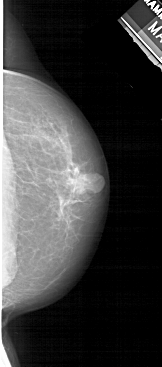

A_1545_1.LEFT_MLO

LEFT_MLO LINES 5491 PIXELS_PER_LINE 2356 BITS_PER_PIXEL 12 RESOLUTION 43.5 OVERLAY